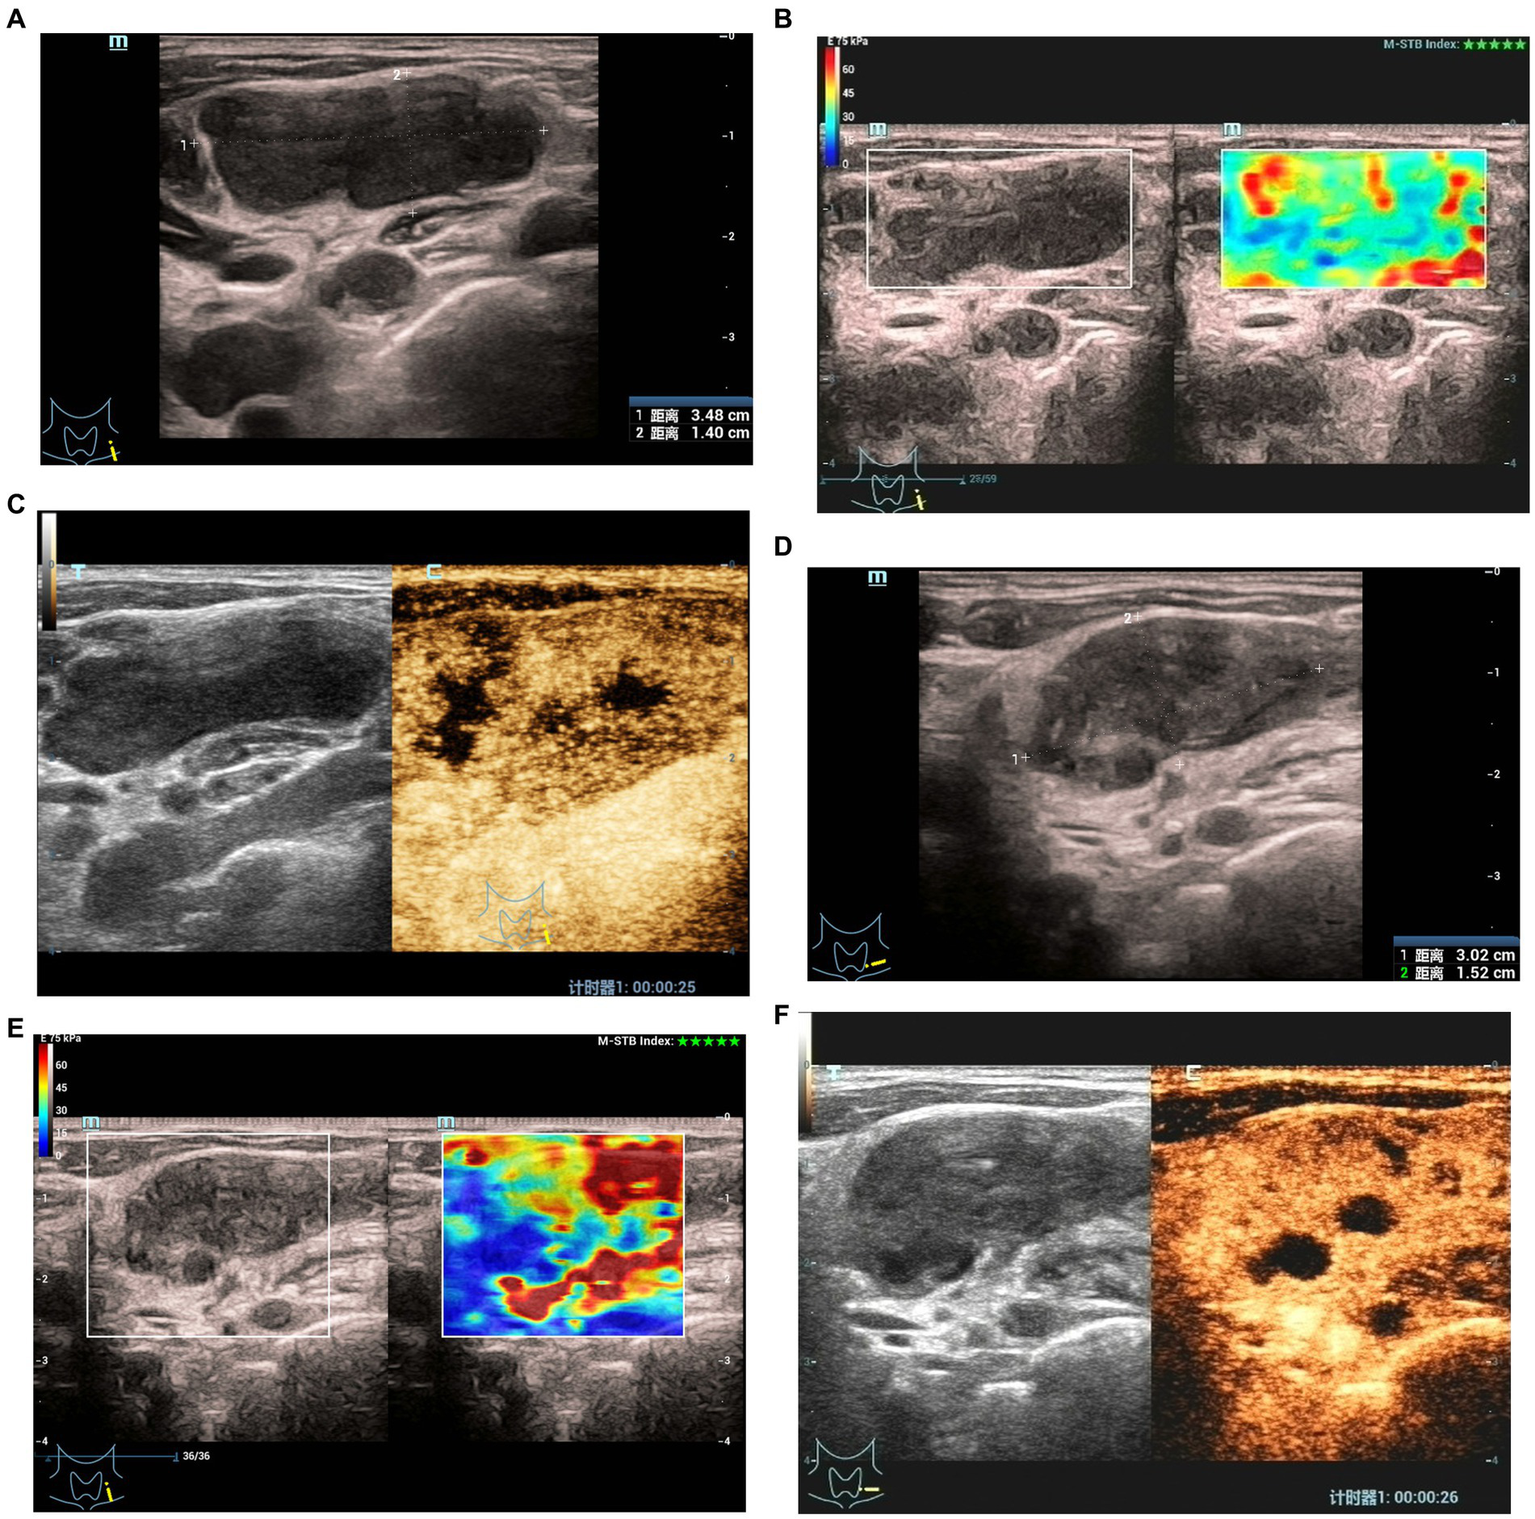

At 1–2 months after treatment, the maximum diameter of lymph nodes in the ineffective group was significantly larger than that in the effective group (p < 0.05). There were significant differences in pus changes, CDFI, elasticity scores, echo of surrounding tissues, changes in enlarged and non-enhanced areas after contrast enhancement between the two groups (Figures 1, 2) (p < 0.05). There was no significant difference in calcification and ring enhancement of lymph nodes between the two groups (p > 0.05), as shown in Table 4.

Figure 2

Elastographyic score and CEUS of an 27-year old man with CTL in the effective group. Before treatment: (A) There was an enlarged left cervical lymph node with a maximum diameter of 3.5 cm and internal heterogeneity, and the echo of the surrounding soft tissue was not changed. (B) Elasticity score was 1. (C) CEUS showed irregular necrotic areas; After treatment: (D) The maximum diameter of the lymph node was 3.0 cm, and the echo of the surrounding soft tissue was hyperechoic. (E) Elasticity score was 2. (F) CEUS showed that the irregular necrotic area was reduced.